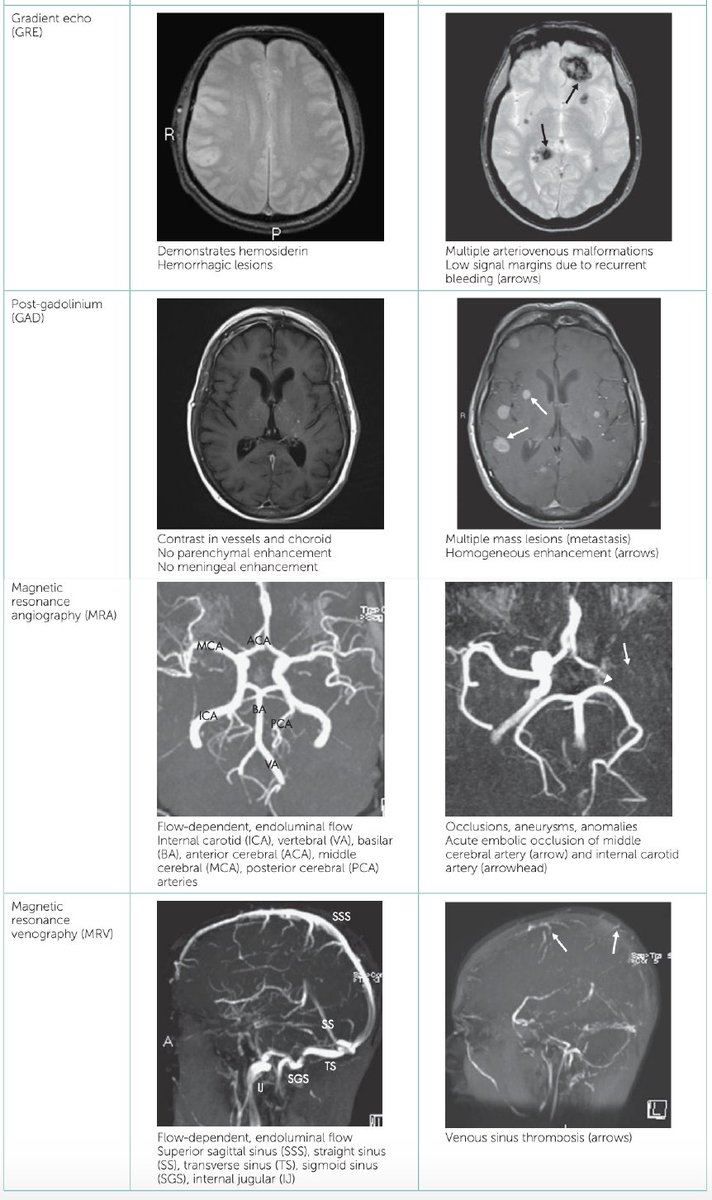

#MRI sequences in the #brain Credit:Essentials of Internal Medicine #radiology #radiography #FOAMrad #radres #neurotwitter #radtwitter #MedTwitter #MedEd #INNOMed #FOAMed

#MRI sequences in the #brain

Credit:Essentials of Internal Medicine